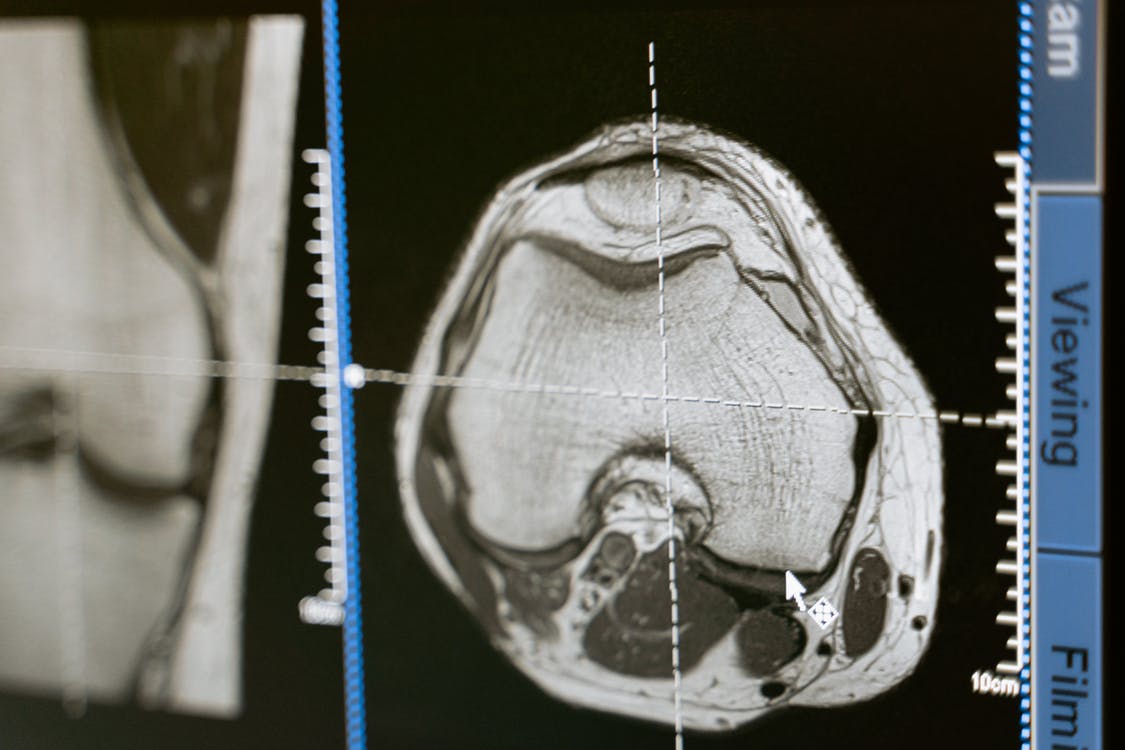

[2] Image retrieved from https://images.pexels.com/photos/7089298/pexels-photo-7089298.jpeg?auto=compress&cs=tinysrgb&h=750&w=1260